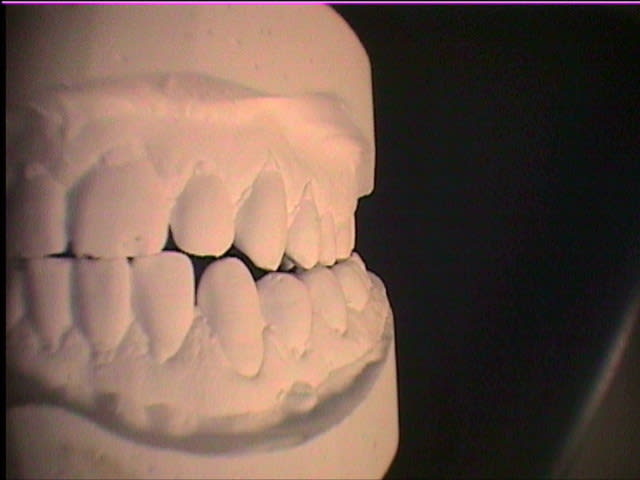

Si vous permettez je commence ça tombe bien je voulais poster ce cas dans les cas cliniques, mais vu que le problème est surtout occluso. Voilà

Patient 45 ans bruxisme, douleurs masseters.

Les points noirs sont les contacts en PIM.

Quelques precisions: peux-tu mettre photo modeles en occlusion face et profils? Afin de voir si décalage mandibule à droite ou à gauche, voir si béances (ou du moins pas de contacts antagonistes), voir rapports dentaires (articulé inversé....).Si y'a des dents traitées précise lesquelles (soins restau, endos, coiffes...).